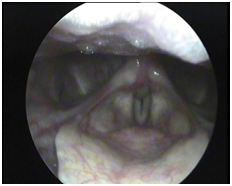

A 35yrs old male patient presented to our ENT OPD with a complaint of progressive hoarseness with gradual voice loss over the 3months. He had symptoms of extra oesophagel reflux and had history of PND and sneezing. On direct laryngoscopic examination with 70degree endoscopy, a granulomatous fleshy growth was observed from medial surface of the right vocal process of arytenoids cartilage. The vocal fold mobility was restricted due to mass effect but there was no stridor or any sign of respiratory distress.

Vocal process granuloma (VPG) is a troublesome problem for the patients, speech language pathologists, and the ENT doctors.7 Aetiologies include voice abuse, gastroesophageal reflux, and endotracheal intubation. Diagnosis of contact granuloma is simple to perform by means of clinical examination alone, because of its characteristic location and peculiar appearance. No other tests are necessary. Biopsy is performed if malignancy is suspected. Despite its name, contact granuloma is not a granuloma in the pathological sense. On light microscopy of the specimen, we may see some focal ulceration, epithelial hyperplasia, necrotic tissue, acute and/or chronic inflammation, capillary proliferation, fibrosis, and partially necrotic arytenoid cartilage.8 A grading system has been proposed on the basis of endoscopic appearance of the granuloma. Grade 1 lesion is limited to the vocal process, with no ulceration in a sessile lesion. Grade 2 lesion is limited to the vocal process and is a ulcerated or pedunculated lesion. Grade 3 lesion extends beyond the vocal process but does not cross the midline of the fully abducted vocal fold. Grade 4 lesion extends beyond the vocal process and crosses over the midline of the fully abducted vocal fold. Unilateral cases are designated as “A” and bilateral ones as “B”.9 The granuloma in our case report had a grading of 4A.